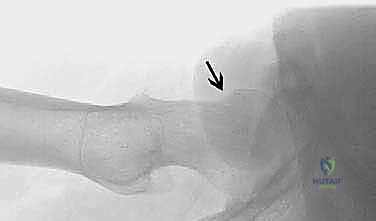

- Osteochondral Autograft Transfer for Talar Dome Lesions: An Operative Masterclass